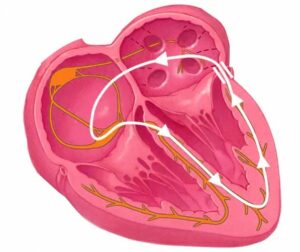

Wolff-Parkinson-White syndrome (WPW) is a heart condition caused by an extra electrical pathway in the heart. In a normal heart, electrical signals travel from the heart’s upper

chambers (the atria) to the lower chambers (the ventricles) through a single, carefully regulated route. In WPW, there is an additional, unregulated pathway — called an accessory

pathway or “bundle of Kent” — that can allow electrical signals to bypass the normal route and cause the heart to beat abnormally fast.

– Electrocardiogram (ECG): The diagnosis of WPW is made on a standard 12-lead ECG. The accessory pathway produces a characteristic pattern, a “delta wave” (a slurred upstroke at the beginning of the QRS complex) and a shortened PR interval. An experienced Paediatric Cardiologist like Dr Giardini can identify this pattern at a glance.

– Electrophysiology study (EPS): In children who are being considered for treatment, a more detailed test performed by passing fine catheters into the heart to map the electrical

pathways in detail. This is both diagnostic and the first step of curative treatment.

Electrophysiological testing can identify features of the accessory pathway, specifically, how rapidly it can conduct electrical signals that stratify risk more precisely. Children with high-risk pathway features, or those with symptoms, are generally offered curative treatment.

This is the definitive and curative treatment for WPW. A cardiologist passes thin, flexible catheters through blood vessels into the heart and delivers precisely targeted

radiofrequency energy (or cryotherapy using extreme cold) to stun and destroy the accessory pathway. The procedure is performed under general anaesthetic in children and typically takes 2–4 hours. Success rates for catheter ablation in WPW are very high — around 95% or above in